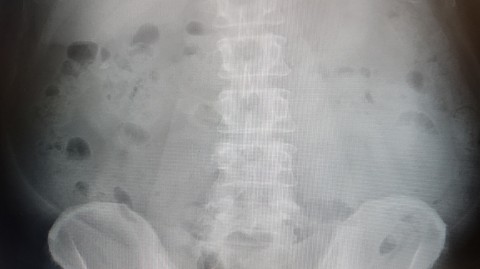

¥ì¥ó¥È¥²¥ó»£¤Ã¤Æ¤ß¤¿¡£¤É¤¦¤â¾å¹Ô·ëIJ¤Ç¤Î·Æ¼¼±ê¤ß¤¿¤¤¡£

¤¤¤Ä¤â¤Ï²£¹Ô·ëIJ¤Ê¤Î¤Ç¡¢°ã¤¦¾ì½ê¤¬±ê¾É¤òµ¯¤³¤·¤¿¤è¤¦¤Ç¤¹¡£

·Æ¼¼¤Ï¤¢¤Ã¤Á¤³¤Ã¤Á¤Ë¤¢¤ë¤Î¤Ç¡¢ÇúÃÆÊú¤¨¤Æ¤ë¤è¤¦¤Ê¤â¤ó¤Ç¤¹¤Í¡£